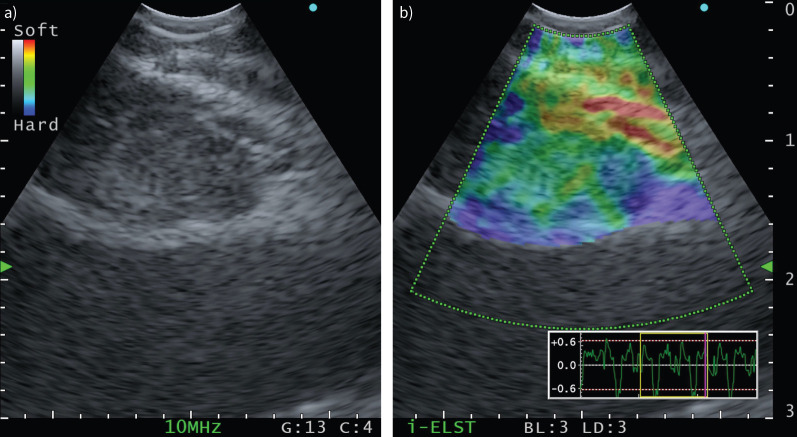

A 69-year-old man with generalised lymphadenopathy, glandular swelling and pleural effusion.

Patients with multisystemic presentation including respiratory symptoms and generalised lymphadenopathy should alert the clinician to this potential diagnosis https://bit.ly/4eJ0PHT.